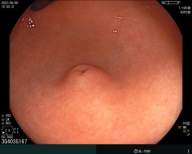

胃内粘膜下隆起,术前结合我科超声内镜,诊断考虑异位胰腺。

89岁高龄患者,诊断胃早期肿瘤,行胃镜下微创治疗(ESD),创伤小,恢复快,保留完整器官。

行内镜粘膜下挖出术(ESE)治疗,术后行荷包缝合,杜绝术后并发症。